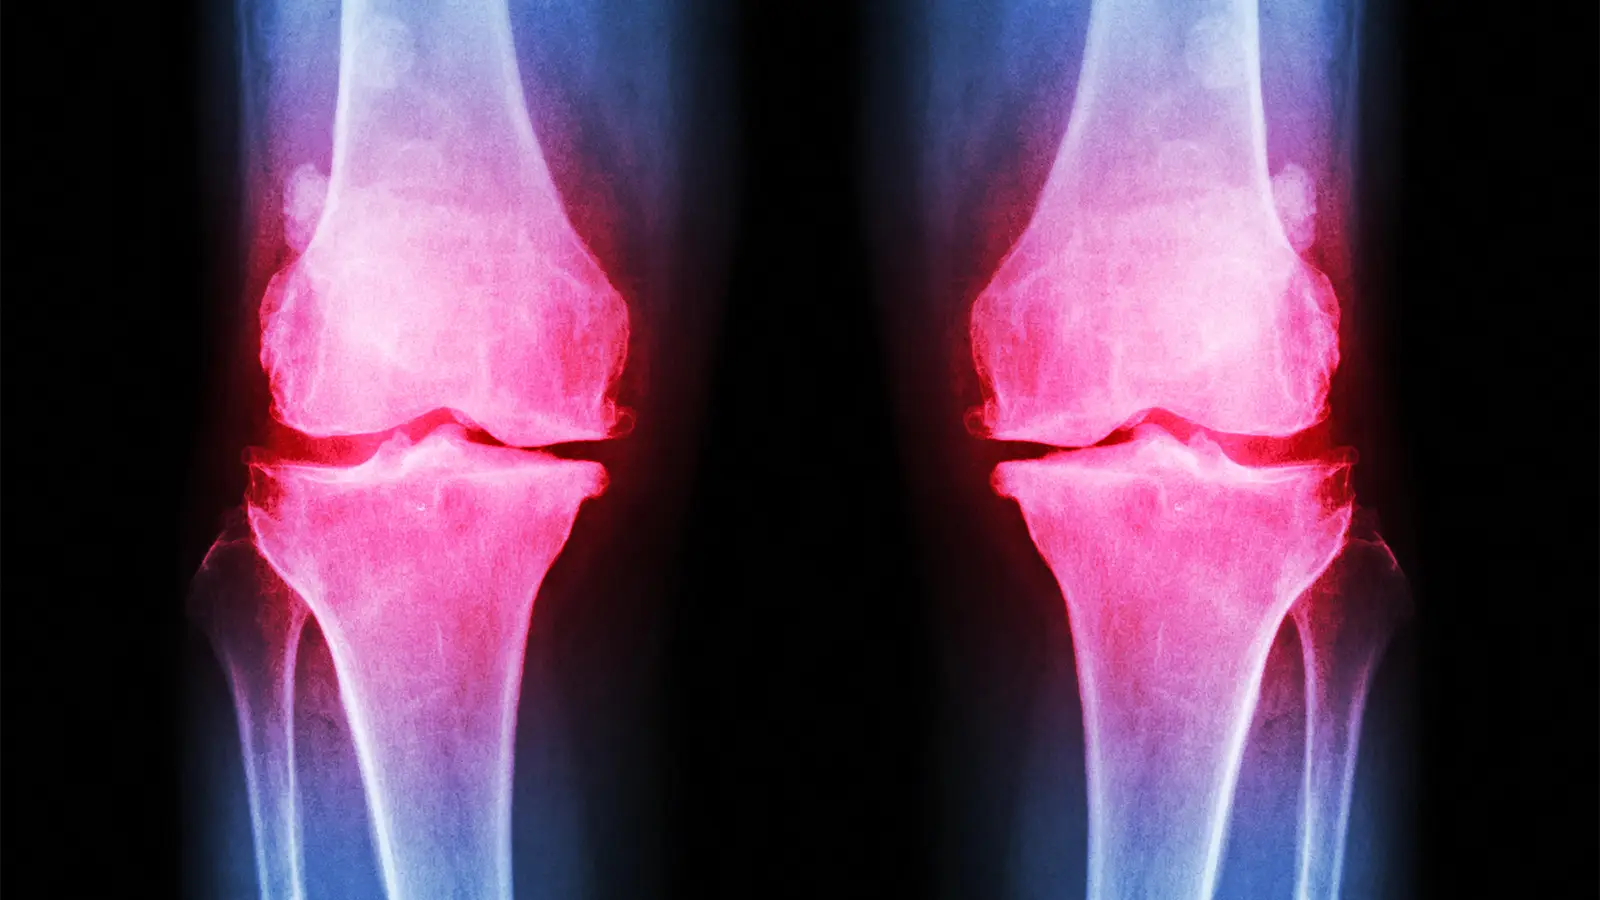

An investigational infusion drug provided more pain relief for patients with osteoarthritis (OA) of the knee than did placebo in a 17-week, phase II clinical trial, researchers said.

Conaghan and colleagues randomized 518 patients from four European countries and Hong Kong with knee OA in equal numbers to receive infusions of placebo or LEVI-04 at one of three doses, given monthly through week 16. WOMAC scores for pain, function, and stiffness were calculated at weeks 5 (after two doses) and week 17 (four doses). Radiographic analyses were performed at baseline and week 20; adverse effects were tracked to week 30.

Mean patient age was about 64 and a little over half the sample were women. WOMAC pain scores in the target knee at baseline averaged 5.74-5.82 in the four study arms; scores in the contralateral knee were about 2 points lower. Half the sample had joint degeneration at baseline rated as Kellgren-Lawrence grade 3 in the target knee, and about 30% were at grade 4.